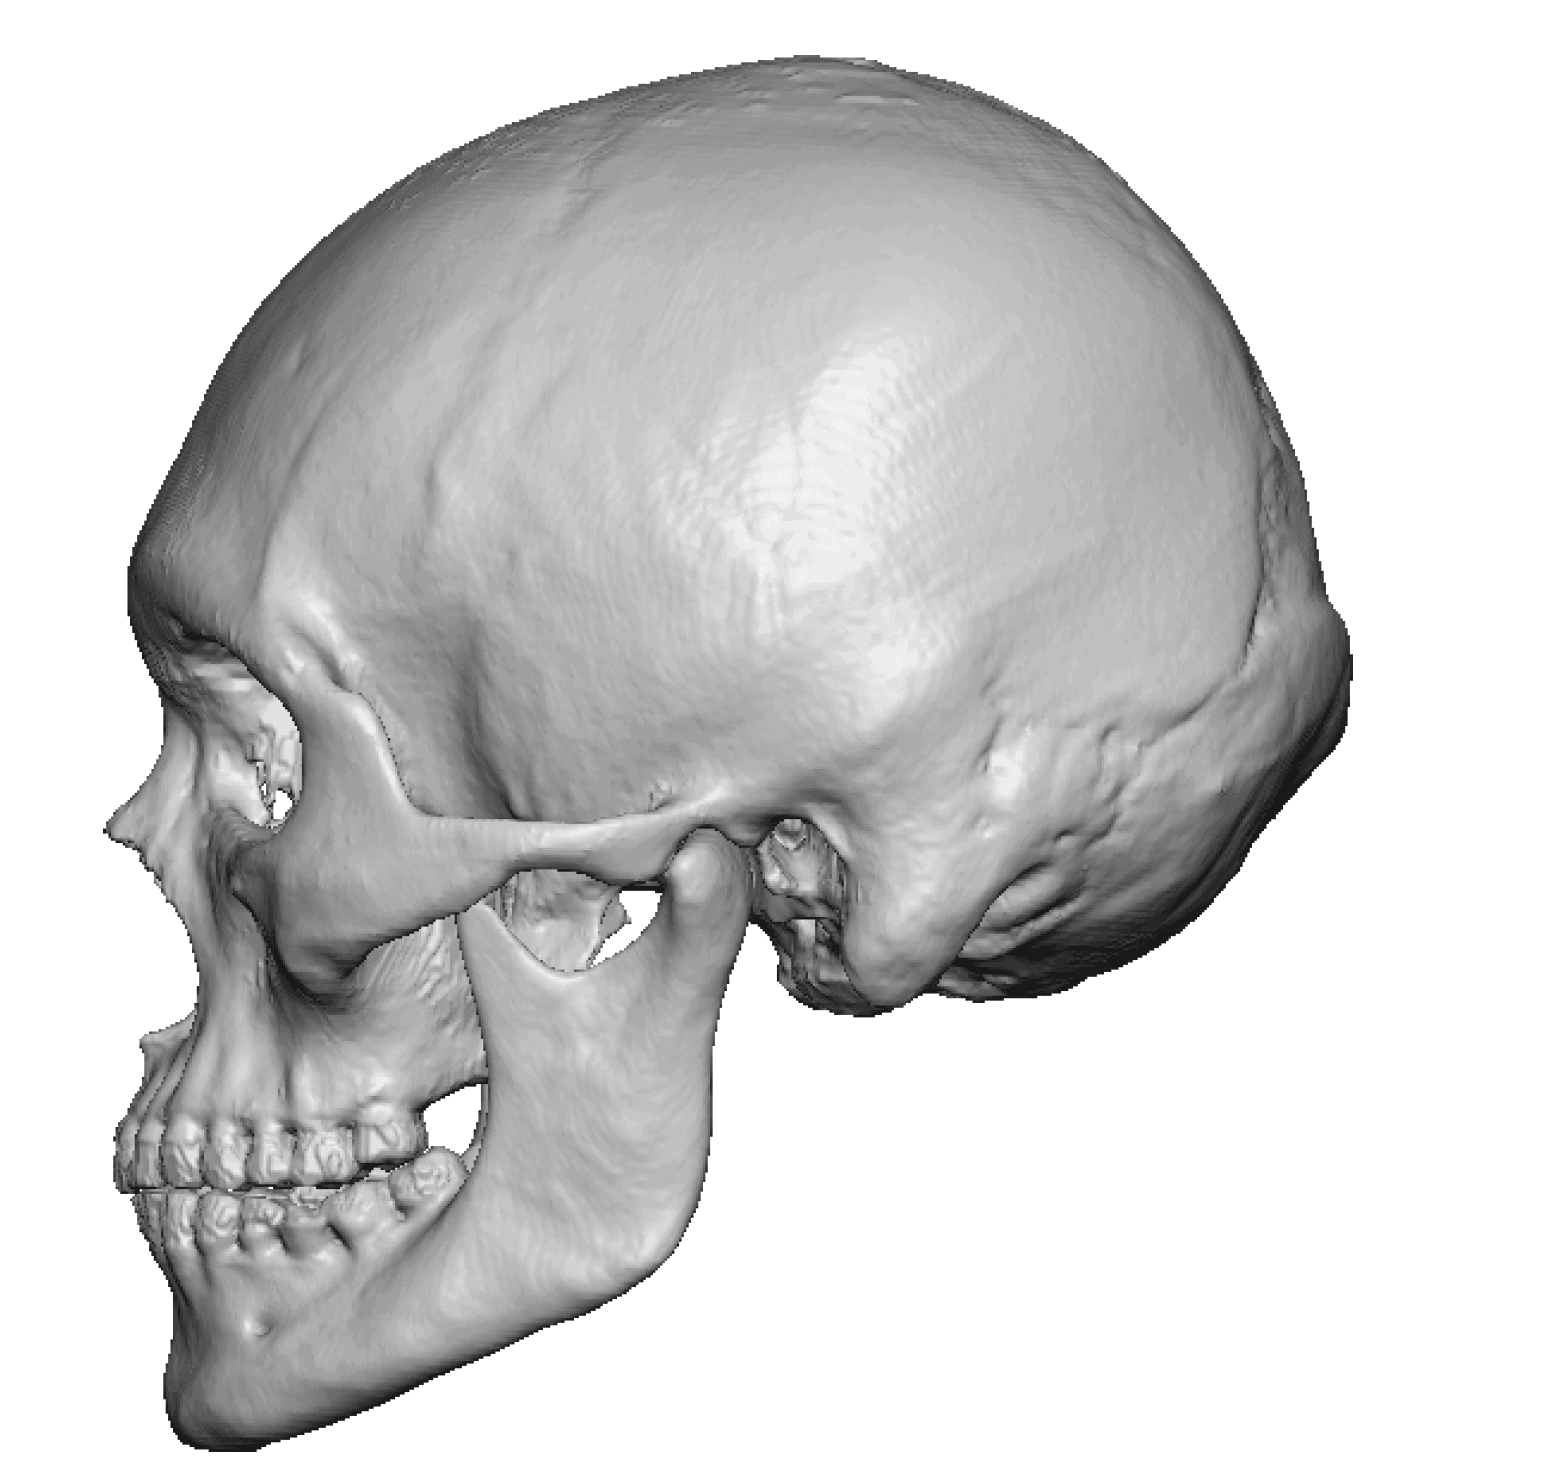

Desire for an improved head shape so that it looks rounder and not so peaked or sloped.

Placement of custom skull implant for parasagittal augmentation to create a rounder head shape. An example of what appears to be a high sagittal crest that is really low parasagittal skull areas.

Desire for an improved head shape so that it looks rounder and not so peaked or sloped.

Placement of custom skull implant for parasagittal augmentation to create a rounder head shape. An example of what appears to be a high sagittal crest that is really low parasagittal skull areas.